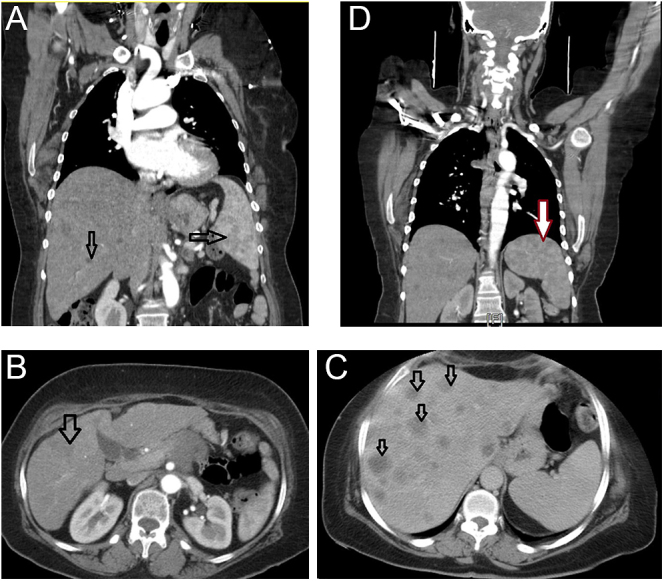

摘要:糖尿病酮症酸中毒(DKA)通常与1型糖尿病或2型糖尿病的急性疾病有关,很少由胰腺腺癌(PA)引发。虽然80%的PA患者有葡萄糖耐受不良,但DKA异常罕见,只有不到20例记录在案。一名新发2型糖尿病的52岁女性患者表现为精神状态改变,腹痛,2个月内体重减轻23公斤。实验室确认DKA(葡萄糖:439 mg/dL, pH 7.1,尿酮)。肿瘤标志物升高(CA19-9: 100 000 U/mL, CEA: 365 ng/mL)和影像学显示胰腺有一个4厘米的肿块并转移,活检证实为PA。本病例强调PA在新发糖尿病中是一种罕见但关键的DKA诱因。不明原因的高血糖、体重迅速下降和肿瘤标志物明显升高应提示恶性筛查。早期多学科干预可能改善这种侵袭性癌症的预后。临床医生必须对不典型DKA表现的隐匿性PA保持高度怀疑。学习要点:不明原因的体重减轻和新发现的2型糖尿病需要彻底评估隐匿性恶性肿瘤。新发糖尿病患者CA19-9和CEA升高应引起对胰腺恶性肿瘤的怀疑。在新发现的2型糖尿病病例中,DKA可能很少作为胰腺癌的初始表现,因此需要高度的临床怀疑。

Summary: Diabetic ketoacidosis (DKA), typically linked to type 1 diabetes or acute illness in type 2 diabetes, can rarely be triggered by pancreatic adenocarcinoma (PA). Though 80% of PA patients have glucose intolerance, DKA is exceptionally uncommon, with fewer than 20 documented cases. A 52-year-old woman with new-onset type 2 diabetes presented with altered mental status, abdominal pain, and 23 kg weight loss over 2 months. Labs confirmed DKA (glucose: 439 mg/dL, pH 7.1, ketonuria). Elevated tumor markers (CA19-9: >10,000 U/mL, CEA: 365 ng/mL) and imaging revealed a 4 cm pancreatic mass with metastases, biopsy-proven as PA. This case underscores PA as a rare but critical DKA precipitant in new-onset diabetes. Unexplained hyperglycemia, rapid weight loss, and markedly elevated tumor markers should prompt malignancy screening. Early multidisciplinary intervention may improve outcomes in this aggressive cancer. Clinicians must maintain high suspicion for occult PA in atypical DKA presentations.